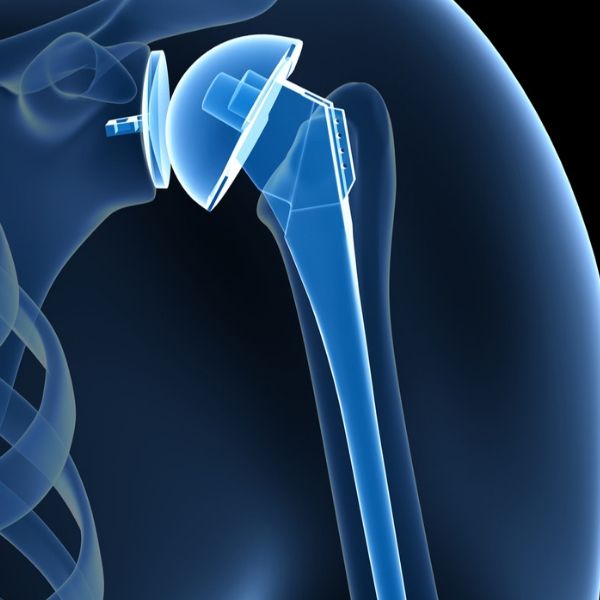

• Χειρουργικής Ώμου και Αγκώνα με έμφαση στην αρθροσκόπηση, την αρθροπλαστική και το τραύμα.